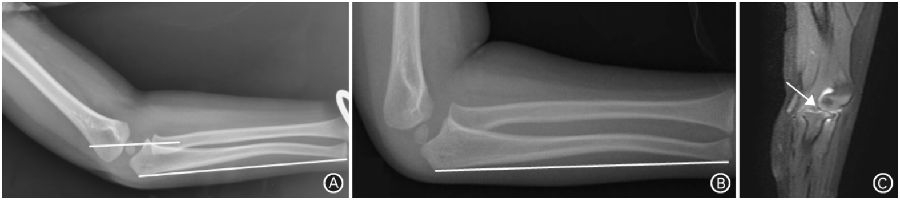

图5 孟氏骨折。A. 伤后即刻侧位X线片示尺骨弯曲骨折,肱桡关节对位对线差,桡骨颈轴线通过肱骨小头上1/3(白色横线),关节软骨不可见;B.伤后4周侧位X线片示明显陈旧孟氏骨折;C.矢状位MRI示肱桡关节之间环状韧带卡压,桡骨头半脱位(箭头所示)

孟氏骨折在临床上同样容易漏诊,可能原因:一是医师主要关注更明显的尺骨骨折,忽略了肱桡关节损伤;二是忽略了单纯尺骨弯曲骨折导致的桡骨头半脱位,此时桡骨轴线常常通过肱骨小头上1/3,MRI可见肱桡关节之间卡压环状韧带或肱二头肌腱(图5)。临床上对孟氏骨折的诊断,参照包括正位X线片上的肱骨外缘线和侧位X线片上的桡骨轴线。正位X线片上肱骨外缘线一般不经过桡骨头,若经过桡骨头,则应考虑孟氏骨折可能。正常侧位X线片上桡骨轴线可经过肱骨小头中或后1/3,不可经过前1/3;若经过前1/3时应考虑孟氏骨折或环状韧带卡压。临床工作中,笔者还发现即使X线片显示肱桡关系对位良好,但后期复查时仍存在再脱位。桡骨头半脱位形成的孟氏骨折,环状韧带多数卡压于肱桡关节之间,患者活动肘关节时引起桡骨头脱位,导致陈旧性孟氏骨折。如果未完全复位卡压的环状韧带而恢复了X线片上的肱桡关系,此时需要投射多种体位验证肱桡关系的稳定性。